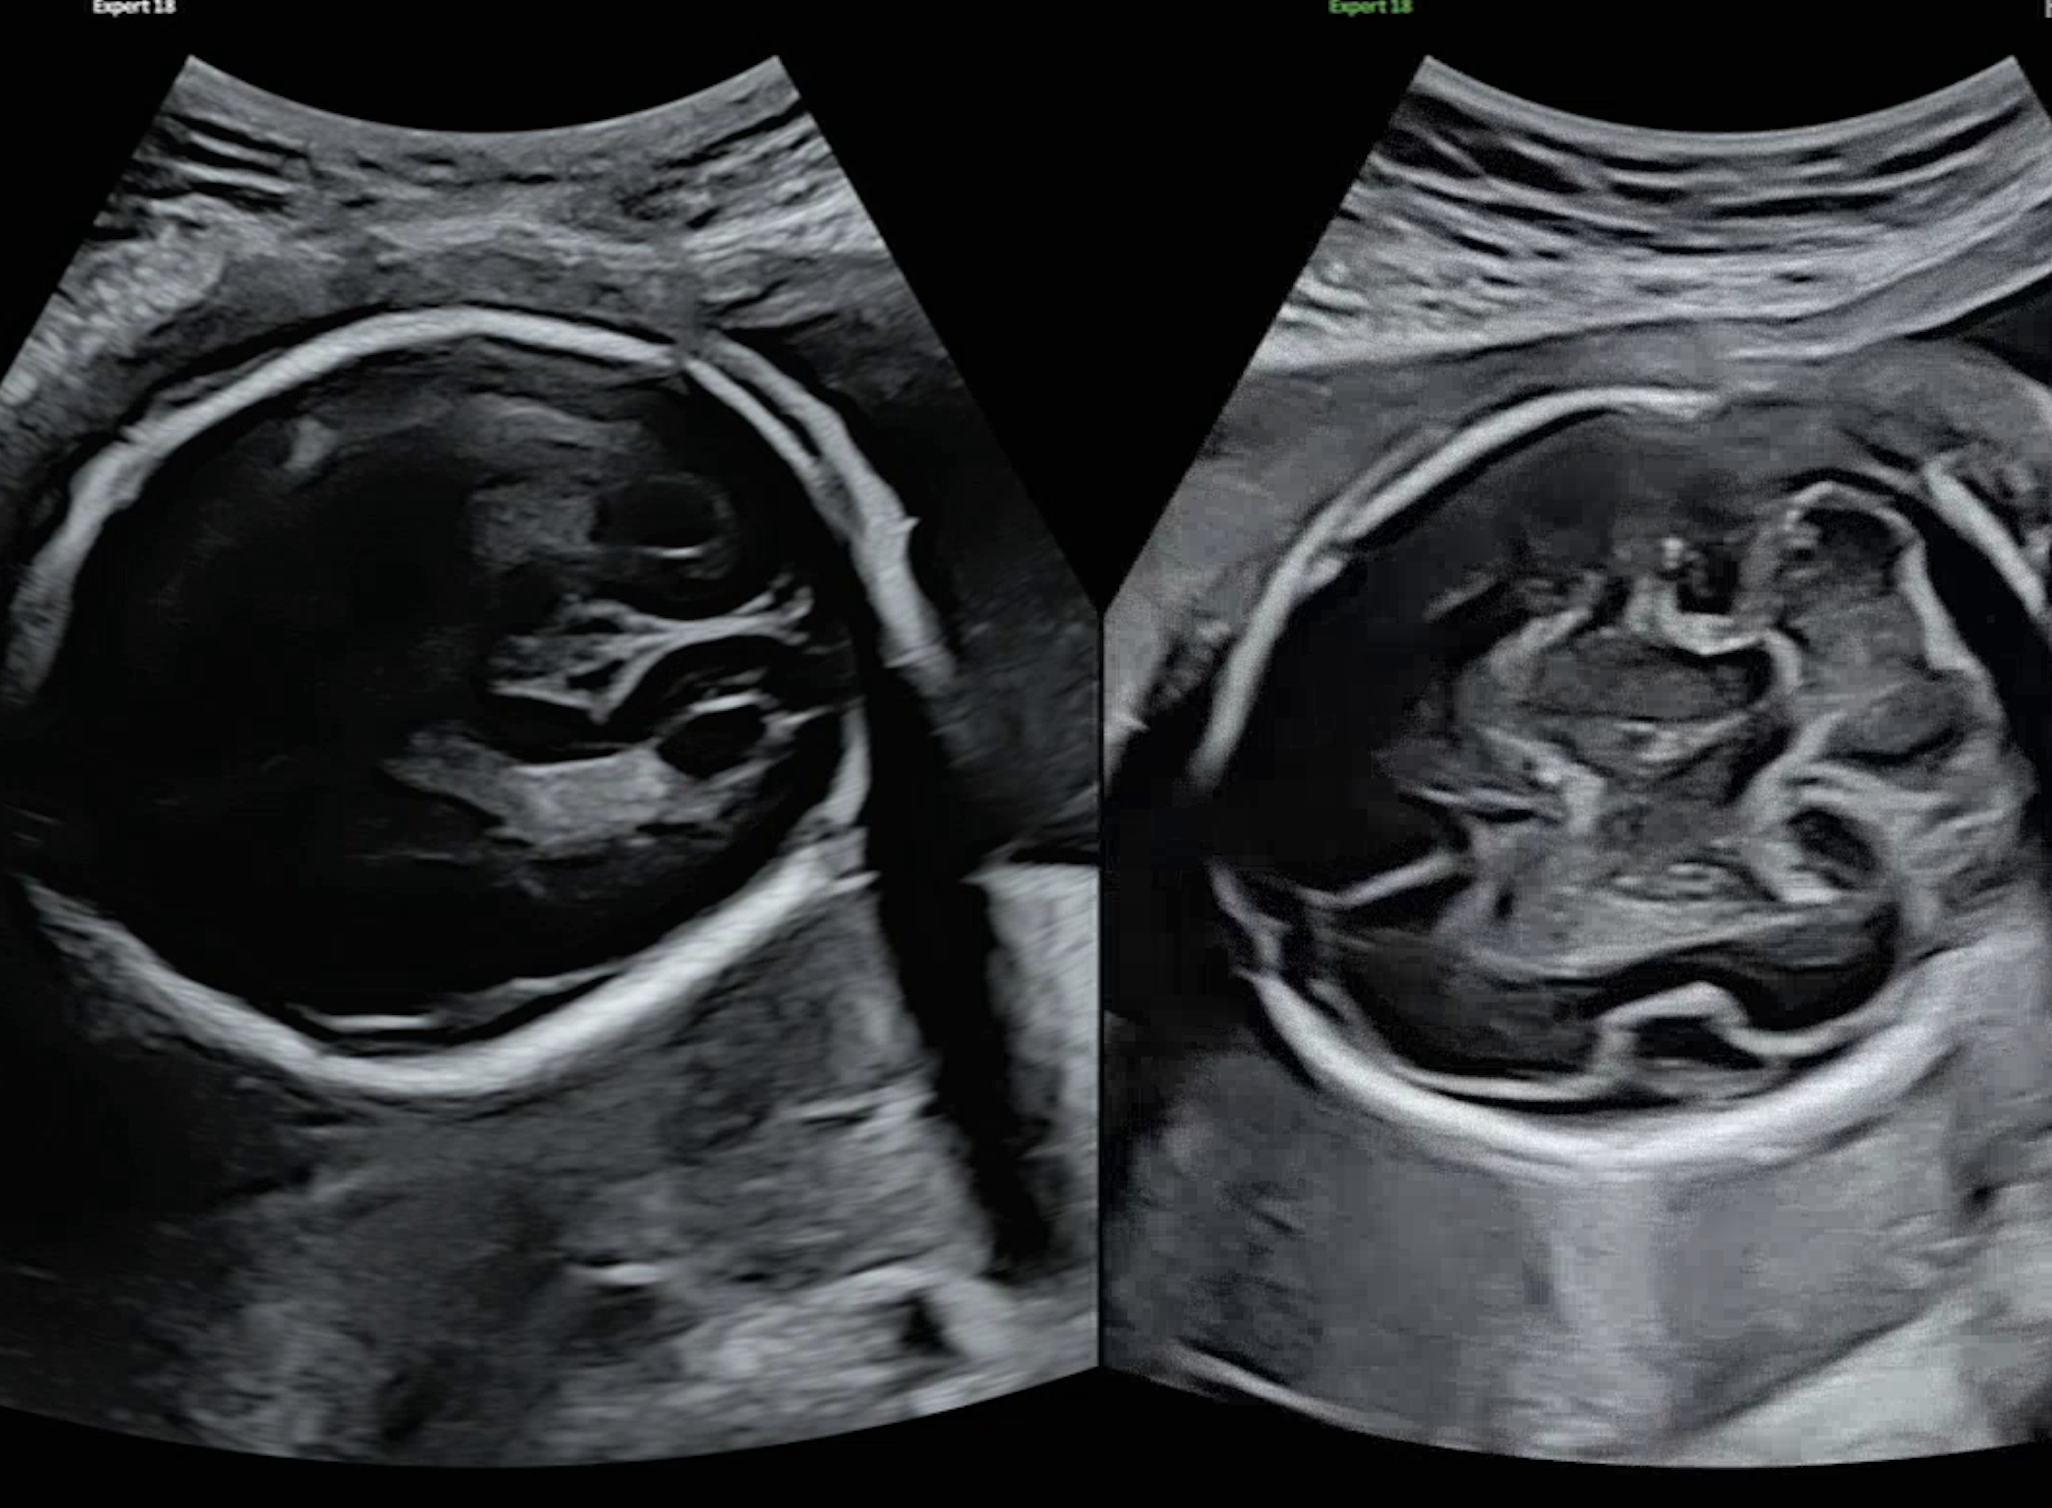

초기에는 초음파 영상이 입체인지 아닌지를 구분하는 것이 핵심 과제였다. 하지만 새로운 서비스 준비와 함께, 이미지 분류 기준을 보다 정교하게 세분화할 필요성이 생겼고, 이는 애초에 내가 지향했던 방향이기도 하다. 단순히 입체 여부를 판단하는 것을 넘어, 영상에 어떤 성장 지표가 (예: AC, BPD, FL) 포함되어 있는지를 구체적으로 분류하고 싶었다. 수많은 시행착오 끝에 구조가 또렷이 보이는 이미지는 ac, bpd, fl 등 긍정 클래스로, 구조 식별이 어려운 이미지는 부정 클래스로 나눠 학습시켰다.

- 1번(데이터 불균형)과 밀접하게 연결돼 있다.특히 세분화된 클래스들 간의 경계가 명확하지 않아, 모델이 어떤 이미지를 어느 클래스에 분류해야 할지 혼란을 겪었던 것으로 보인다. 예를 들어, BPD 와 CEREB (소뇌)은 초음파 영상에서 육안으로 보기에 매우 유사한 경우가 많다. 하지만 학습 데이터를 구성할 당시에는 이러한 경계의 불명확성을 충분히 고려하지 못하고, 내 주관적인 기준에 따라 "감"으로 라벨링을 진행한 부분이 있었다.